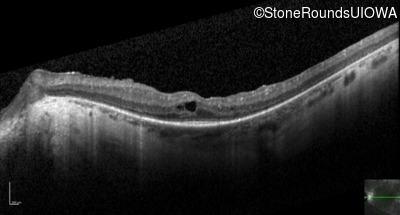

Optical Coherence Tomography - Left - 20/50 -2

Exemplar / OCT Stack

OCT Stack